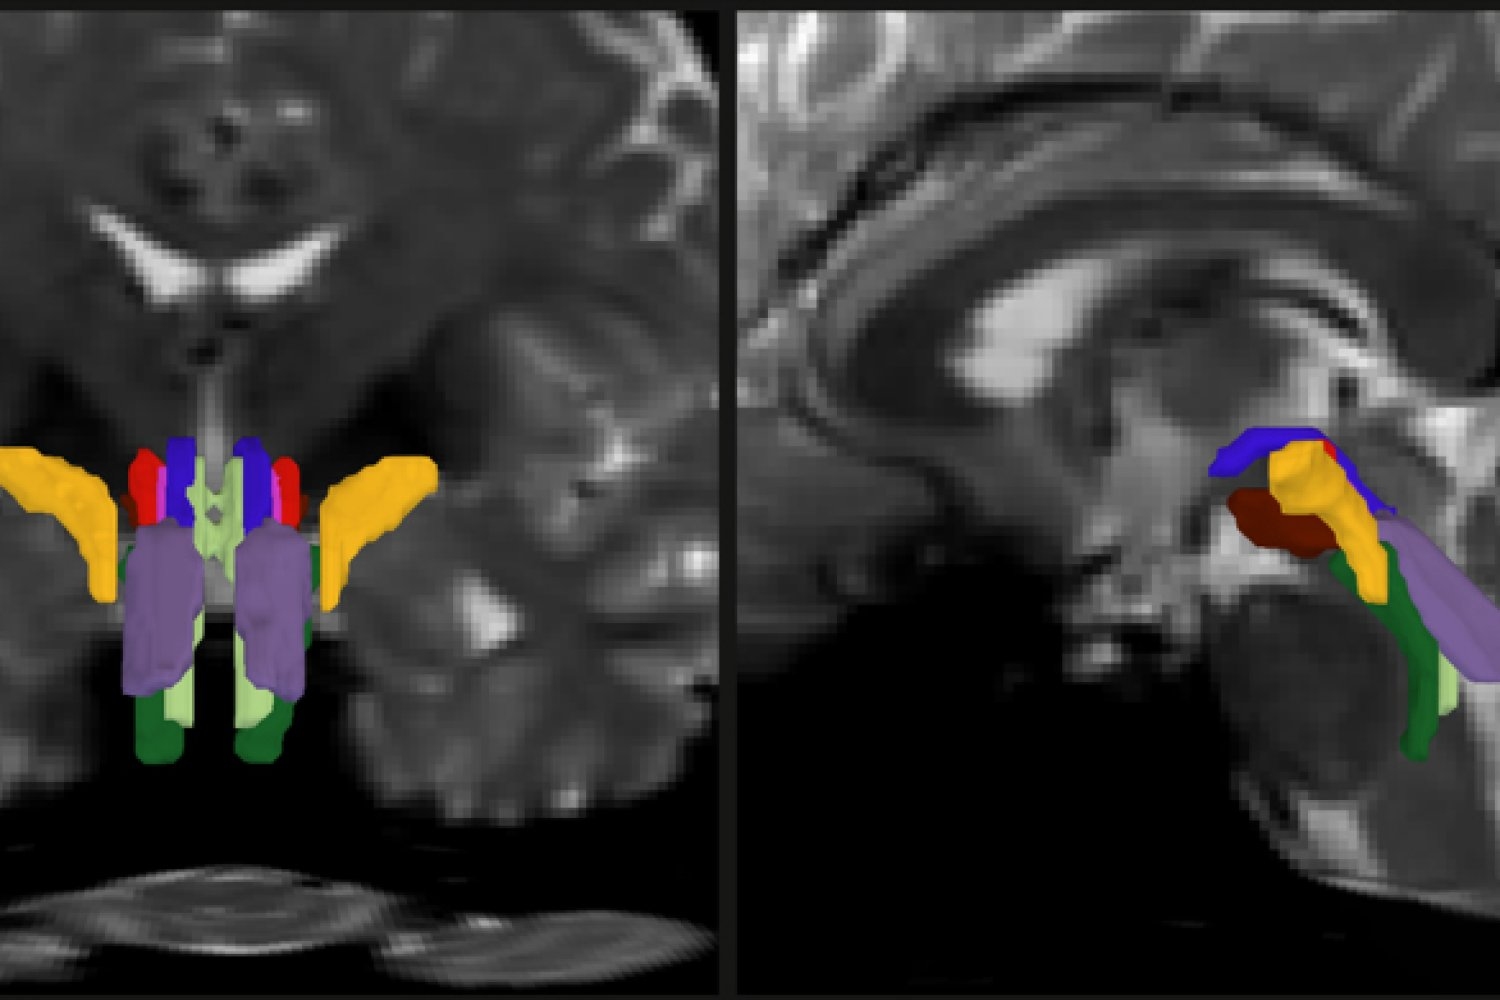

In a new study, a team of MIT, Harvard University, and Massachusetts General Hospital researchers unveil AI-powered software capable of automatically segmenting eight distinct bundles in any diffusion MRI sequence.

As part of his thesis work to better understand the neural mechanisms that underpin consciousness, Olchanyi wanted to develop an AI algorithm to overcome these obstacles. BSBT works by tracing fiber bundles that plunge into the brainstem from neighboring areas higher in the brain, such as the thalamus and the cerebellum, to produce a “probabilistic fiber map.” An artificial intelligence module called a “convolutional neural network” then combines the map with several channels of imaging information from within the brainstem to distinguish eight individual bundles.

To train the neural network to segment the bundles, Olchanyi “showed” it 30 live diffusion MRI scans from volunteers in the Human Connectome Project (HCP). The scans were manually annotated to teach the neural network how to identify the bundles. Then he validated BSBT by testing its output against “ground truth” dissections of post-mortem human brains where the bundles were well delineated via microscopic inspection or very slow but ultra-high-resolution imaging. After training, BSBT became proficient in automatically identifying the eight distinct fiber bundles in new scans.